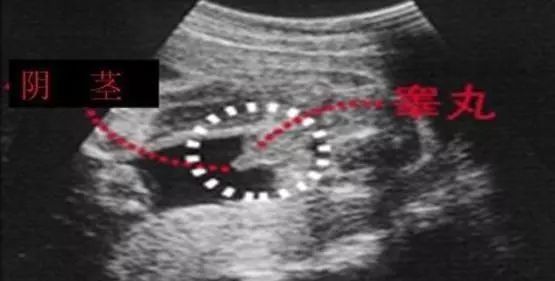

男宝宝B超图

“凸出的东西”是他的标记:你们看到圆圆的是DANDAN,如果看到圆圆的加小肠的就是全部JJ